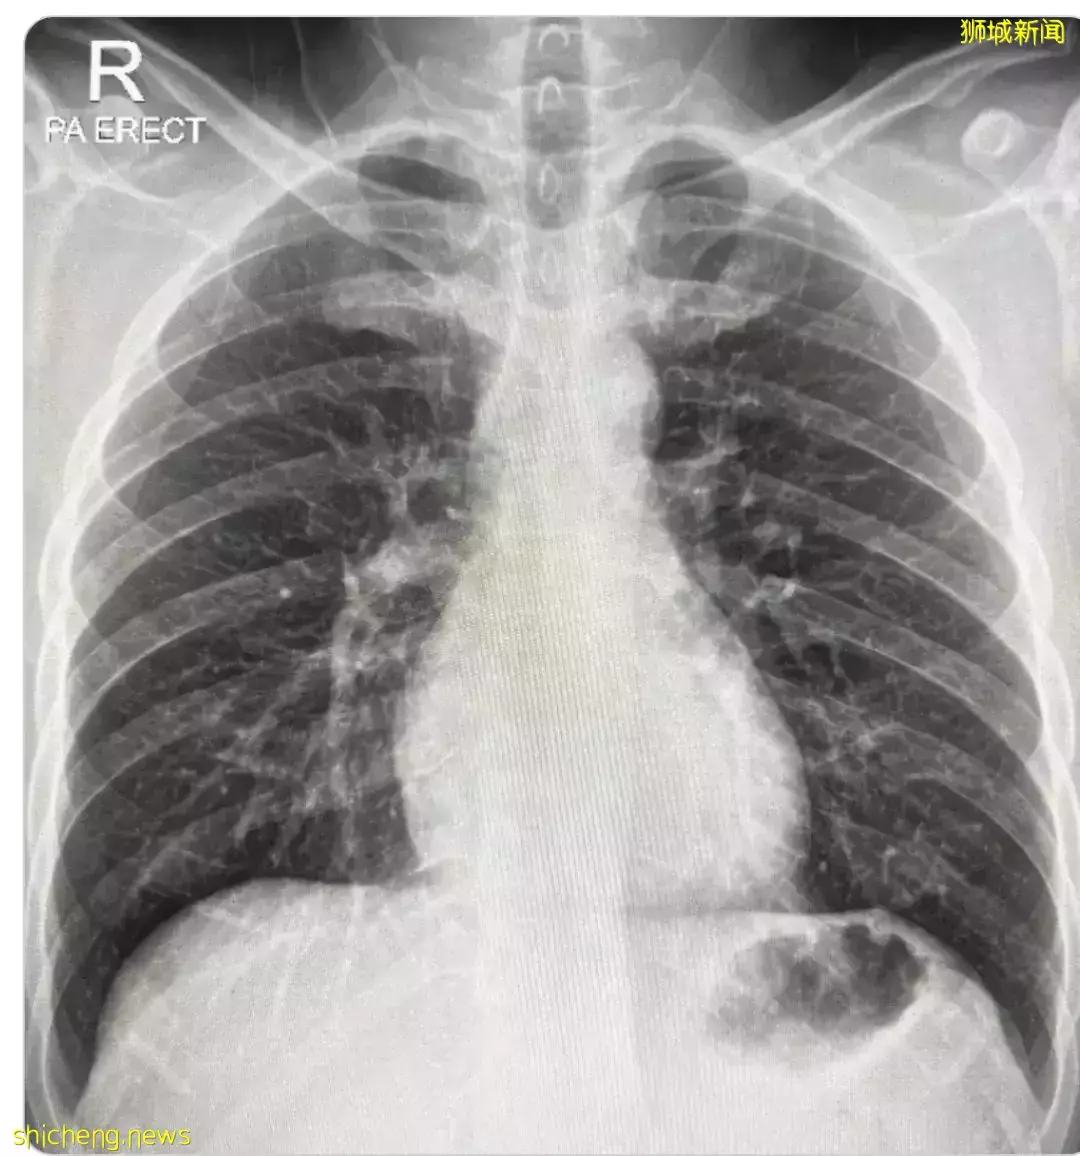

医生建议他做一个肺部X光。

没想到,照出来肺部竟然有轻微结疤,意味着肺脏受到损伤并开始纤维化。

有人跟他有同款经历,晒出了跟他类似的肺部X光照片。

一般情况下,正常人的肺部断层扫描应该要呈现黑色,代表充满空气,但是曾经发炎并留下疤痕组织的肺则会是一片白色。

且肺不像其他器官一样能够再生,因此这些疤痕恐怕会伴随病人的一生。”